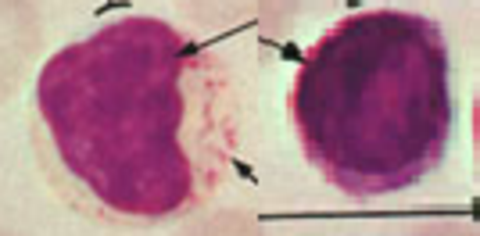

Monocyte

Reconisable Features- Monocyte Small, pale granules, folded brain-like nucleus, abundant cytoplasm

Role- Monocytes Phagocytosis